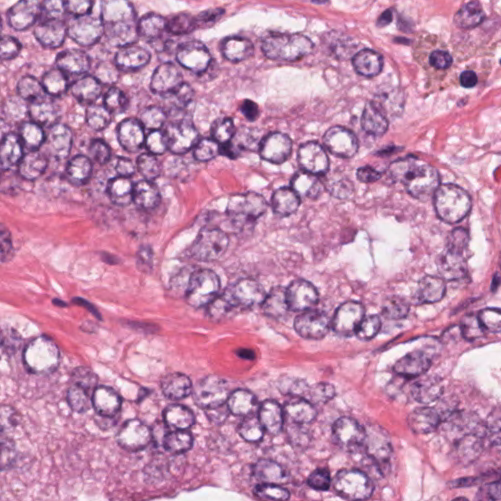

As an essential part of digital pathology, histopathology image analysis is playing increasingly important role in cancer diagnosis, which can provide direct and reliable evidence to diagnose the grade and type of cancer. This paper deals with nuclei segmentation, an important step in histopathological image analysis. The purpose of nuclei semgentation is not only counting the number of nuclei but also obtaining the detailed information of each nucleus. So unlike nuclei detection, here the outputs are the contour of each nucleus instead of only the position of their central points. Hence we can exactly extract each nucleus from the image and make it available for further analysis. For example, the features of the individual nucleus and the distribution of nuclei clusters can be used to grade and classify status of breast cancers [3, 4]. Because of appearance variation such as color, shape, and texture, nuclei segmentation from histopathological images could be very challenging, as illustrated in Fig.1, in which it is very challenging even for human to recognize and segment all nuclei within the images. Fig.1(a) and Fig.1(b) illustrate two histopathological images from different organs. Fig.1(c) and Fig.1(d) are two histopathological images from same organ but have different cancer grade.